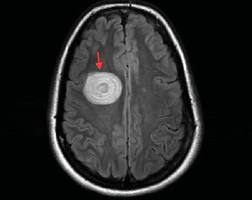

• Σκλήρυνση σημαίνει ουλές: αυτές είναι πλάκες ή ελλείμματα στον εγκέφαλο και τον νωτιαίο μυελό.

• Στην ΣκΠ, καταστρέφεται η προστατευτική μυελίνη που καλύπτει τις νευρικές ίνες του ΚΝΣ.

• Η φλεγμονή και η απώλεια της μυελίνης, προκαλούν τις διαταραχές στην μετάδοση των ερεθισμάτων και επηρεάζουν πολλές λειτουργίες του σώματος.